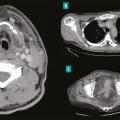

Les infections cutanées graves sont principalement représentées par les infections nécrosantes des tissus mous ou dermohypodermites bactériennes nécrosantes-fasciites nécrosantes (DHBN-FN). Bien que rares, elles sont associées à une mortalité élevée et à de lourdes séquelles à long terme. La principale difficulté réside dans l…

Les infections nécrosantes des tissus mous sont un groupe hétérogène de pathologies dont la diversité physiopathologique découle notamment d’une diversité microbiologique (infections monomicrobiennes à streptocoque du groupe A ou à Clostridium difficile, infections polymicrobiennes à entérobactéries…) et anatomique (pyomyosite,…